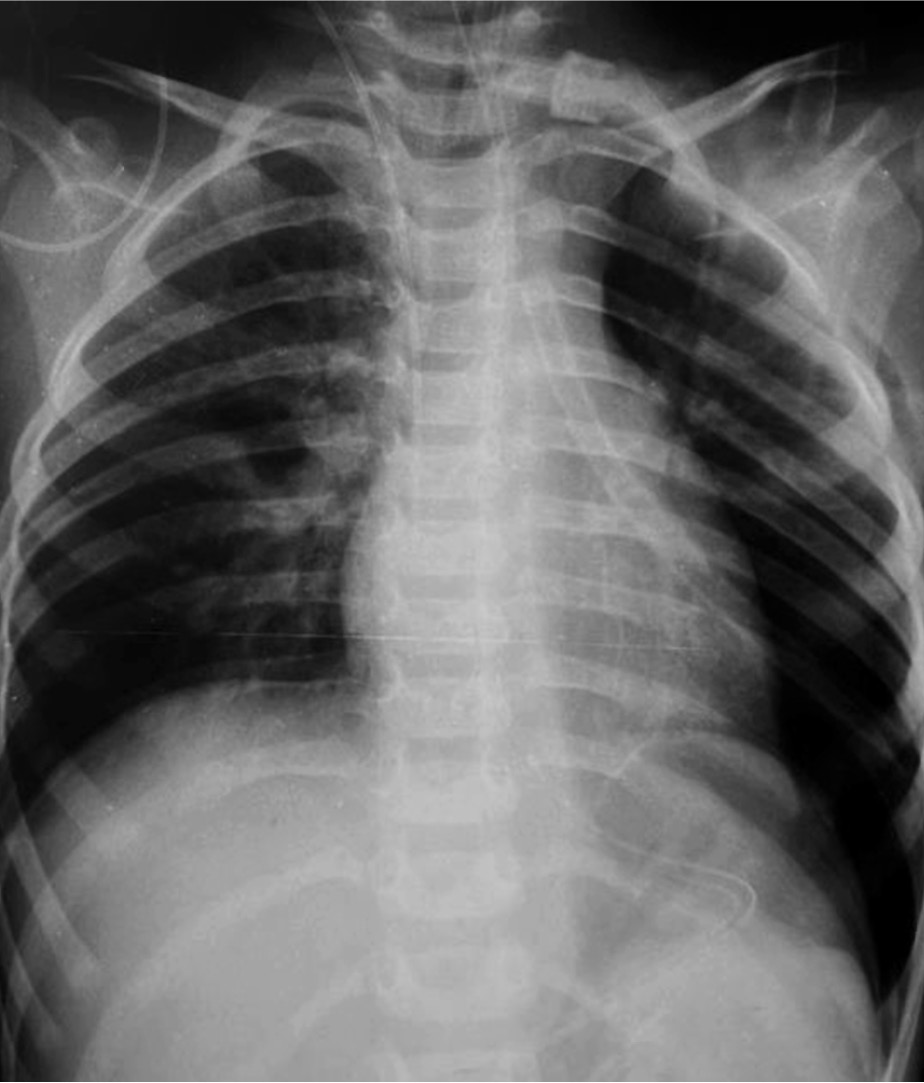

В послеоперационном периоде ребёнок получал инфузионную, симптоматическую и антибактериальную терапию. На 6 сут после операции выполнена контрольная обзорная рентгенограмма органов грудной клетки: лёгкие расправлены, средостение не смещено, контур левого купола диафрагмы прослеживается на всём протяжении (рис. 3). При аускультации дыхание пуэрильное, симметричное, с некоторым ослаблением слева в нижних отделах.

Рис. 3. Контрольная обзорная рентгенограмма органов грудной клетки после операции.

Fig. 3. Control plain-film X-ray of chest organs after surgery.